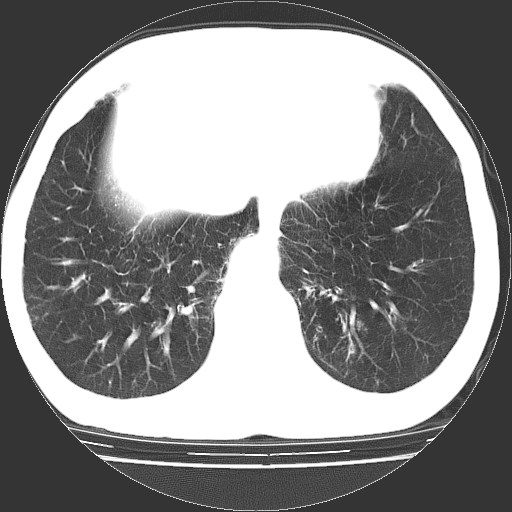

以下是引用hhcckk在2009-1-1 15:38:00的发言:[br]左下肺少许絮状模糊影--考虑感染[br]两肺散在小点状密度增高影--结合病史考虑矽肺?[br]气管壁钙化--可能由于老年退变性引起的